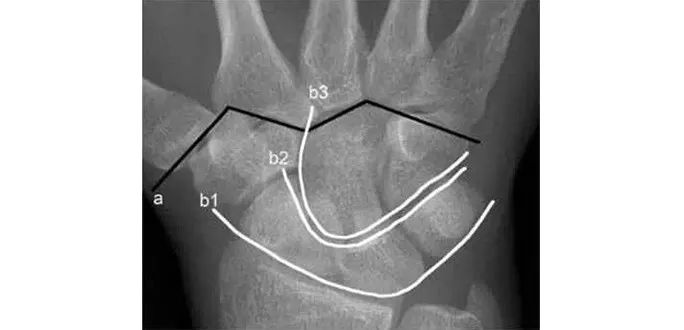

两条弧线如果不连通多半有脱位

若显示腕骨弧线不连续或各弧线不平行,或腕掌线M 形结构消失,应高度怀疑腕关节不稳或脱位。